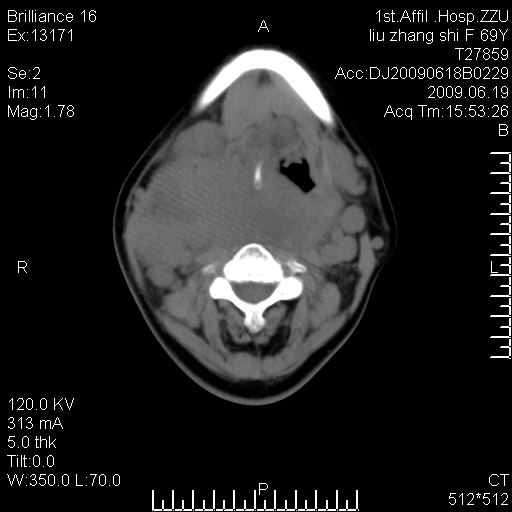

标题: CT26782:女,69岁,颈部占位,3天后公布病理结果。

【病理证实系列】女,69岁,颈部占位,有病理结果,3天后公布。(由于病例时间较久,临床资料不全,请网友见谅)本系列将有几百种常见、少见及罕见病例,均经病理证实。病例资料来自郑州大学第一附属医院。与网友共享,本人有空就发。

甲状腺癌并颈部淋巴结转移。感谢楼主的良苦用心,谢谢。

甲状腺癌并颈部淋巴结转移。

需与鼻咽癌鉴别!

支持甲状腺癌广泛侵及周围结构并颈部淋巴结转移。

鉴别:淋巴瘤、恶性神经源性病变、恶性纤维组织细胞瘤。

病理结果:颈部非霍奇金淋巴瘤。